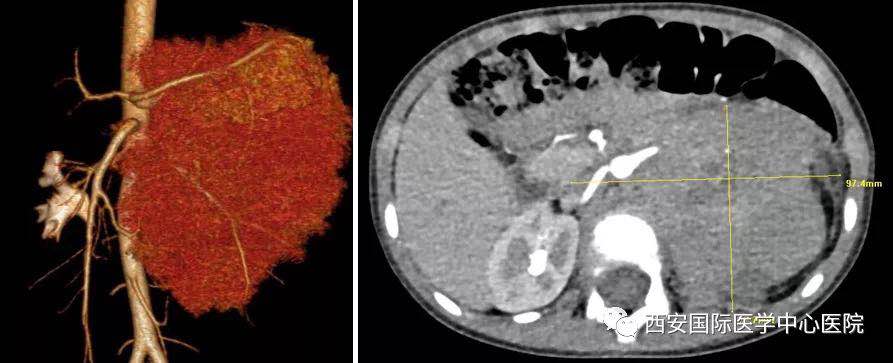

入院后,楊增悅主任仔細詢問病史、查閱影像學資料,第一時間為依依安排骨髓穿刺活檢,最終確診為:腹膜后神經(jīng)母細胞瘤(Ⅳ期/L2)。CT顯示腫瘤巨大,侵及腹主動脈、腹腔干、腸系膜上動脈、雙腎動脈、腸系膜下動脈、下腔靜脈、雙腎靜脈、左腎及腎上腺、胰十二指腸、脾臟、結(jié)腸脾曲;腹膜后多發(fā)淋巴結(jié)轉(zhuǎn)移、骨轉(zhuǎn)移。骨穿病檢示:神經(jīng)母細胞瘤骨髓轉(zhuǎn)移,腫瘤細胞占90.5%。經(jīng)過科室團隊討論后決定,先行新輔助化療后再進行手術(shù)治療。